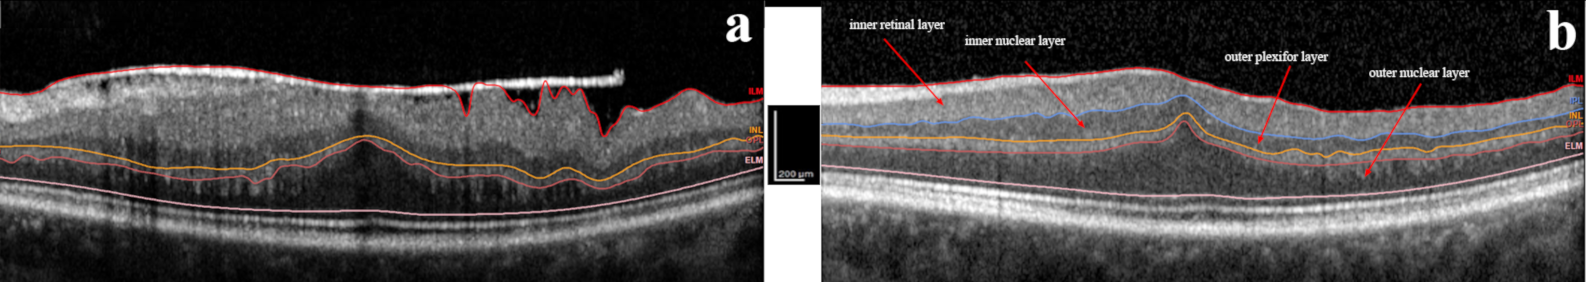

| IRL central | 159.57 ± 46.90 | 111.33 ± 19.16 *** | 102.29 ± 20.39 ** | 100.62 ± 17.41 | −0.31 ± 0.25 | <0.001 |

| Average IRL | 179.7 ± 32.1 | 130.2 ± 16.9 *** | 120.4 ± 17.2 ** | 115.7 ± 16.8 ** | −0.34 ± 0.13 | <0.001 |

| INL central | 87.05 ± 26.19 | 73.14 ± 16.37 *** | 65.57 ± 12.94 ** | 62.10 ± 13.87 ** | −0.25 ± 0.19 | <0.001 |

| Average INL | 70.8 ± 14.7 | 62.3 ± 10.42 | 58.3 ± 8.60 | 55.53 ± 8.07 * | −0.19 ± 0.15 | 0.014 |

| OPL central | 51.48 ± 10.78 | 43.86 ± 9.75 *** | 41.14 ± 7.67 ** | 38.29 ± 6.40 | −0.23 ± 0.15 | <0.001 |

| Average OPL | 47.2 ± 8.0 | 43.0 ± 5.72 *** | 41.5 ± 4.66 * | 39.85 ± 5.92 | −0.14 ± 0.13 | <0.001 |

| ONL central | 128.10 ± 27.34 | 122.10 ± 23.22 * | 118.86 ± 21.69 * | 115.10 ± 19.27 | −0.08 ± 0.14 | 0.005 |

| Average ONL | 91.2 ± 15.8 | 92.9 ± 14.8 | 90.8 ± 13.66 * | 87.28 ± 12.32 ** | −0.03 ± 0.11 | 0.043 |